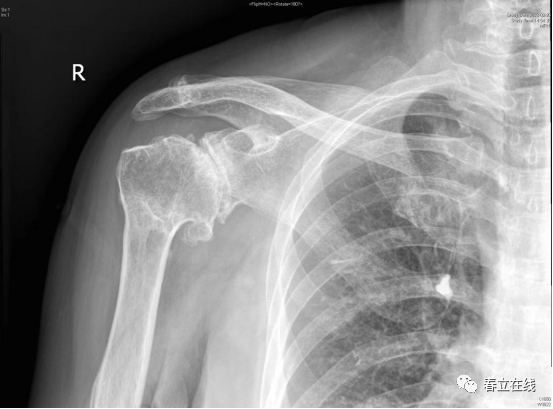

【优选病例】反置式人工全肩关节置换术病例分享

患者1年前无明显诱因下感右肩部疼痛,右肩关节活动受限,曾至当地医院就诊后,行肩关节KI示:右肩袖损伤,右肩关节粘连性肩关节囊炎,右肩关节退变,右侧肩关节积液,予以保守治疗,现感疼痛持续,为求进一步诊治,遂至我院门诊就诊,门诊拟“右侧肩关节骨性关节病+巨大肩袖撕裂“。

该例手术是南通大学附属医院骨科主任王友华教授团队成功为患有右肩关节骨性关节炎的范奶奶实施反置式人工全肩关节置换术术中出血少、创伤小术后范奶奶右肩疼痛消失经过康复训练后手臂可自如活动。